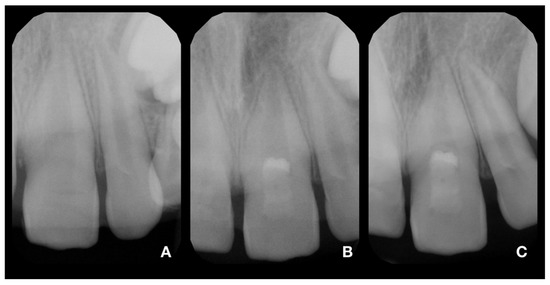

2.2. Partial Pulpotomy and Adhesive Reattachment of Tooth 11

2.3. Deep Pulpotomy and Adhesive Reattachment of Tooth 21 after Flap Reflection

2.4. Follow-Up